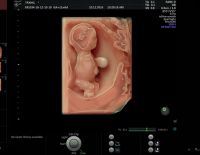

Siêu âm màu là gì? Lợi ích và thời điểm thực hiện siêu âm màu

Siêu âm màu trong thai kỳ giúp cha mẹ lưu giữ được hình ảnh của con từ khi còn trong bụng mẹ để làm kỉ niệm. Ngoài ra còn rất nhiều lợi ích mà siêu âm màu mang lại. Cùng giải đáp những thắc mắc...